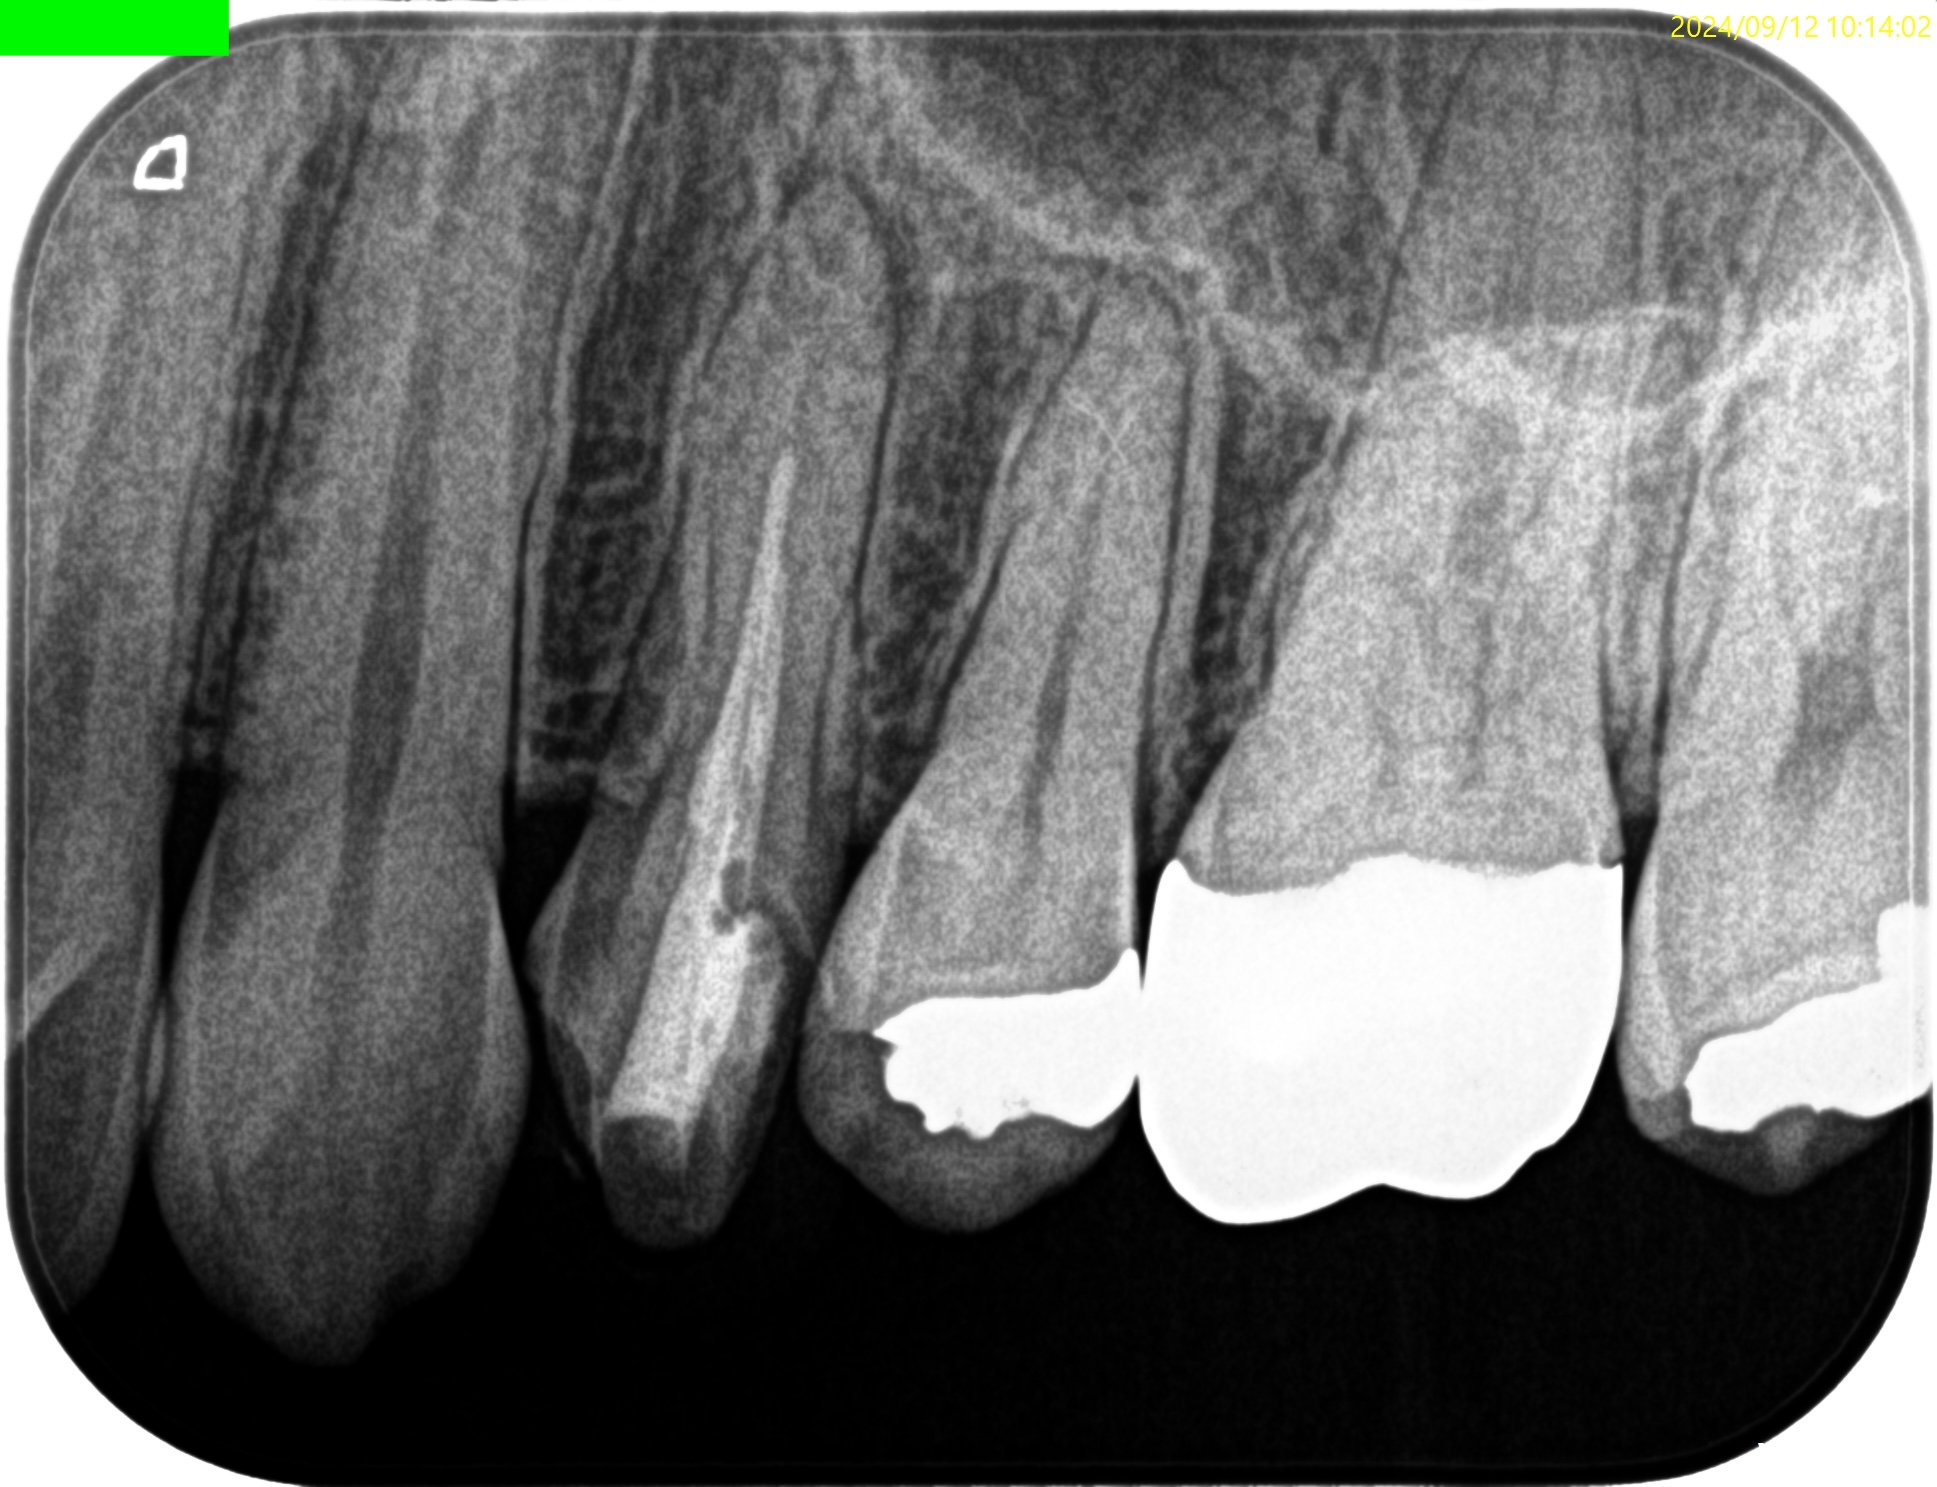

Pre-op Endo Test(2024.3.7)

#12 Cold++1/13, Perc.(+), Palp.(-), BT(-), Perio Probe(WNL), Mobility(WNL)

Pulp Dx: Pulp necrosis

Periapical Dx: Symptomatic apical periodontitis

Recommended Tx: RCT

#12はMTAセメントという魔法の薬で神経を保護したので大丈夫ですよ、と言われたそうだが

大丈夫なのはその人の頭の中だけである。

神経を保護するような治療を行うと、歯髄が石灰化してしまう。